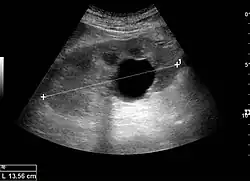

The complex cyst can be further evaluated with doppler ultrasonography, and for Bosniak classification and follow-up of complex cysts, either contrast-enhanced ultrasound (CEUS) or contrast CT is used.[13]

Renal cyst as seen on abdominal ultrasound -